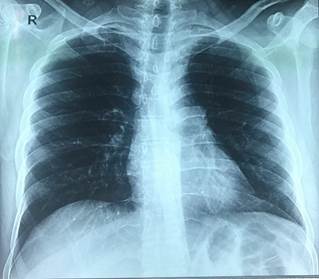

En la Figura 1 se presenta la radiografía de tórax que no tiene hallazgos patológicos.

Este paciente no presentó manifestaciones radiológicas que evidencien una TBC pulmonar primaria: consolidación, tuberculomas, cavitaciones, entre otras 10. Debido al contacto con diferentes grupos poblacionales en los viajes interprovinciales no se puede descartar que el foco primario sea pulmonar silente 9, de no ser el caso, se plantea la inoculación directa. El consumo diario inicial de glucocorticoides explica la causa exógena del síndrome de Cushing y la inmunosupresión que facilitó la posibilidad de la diseminación del bacilo desde la cadera hasta el SNC.